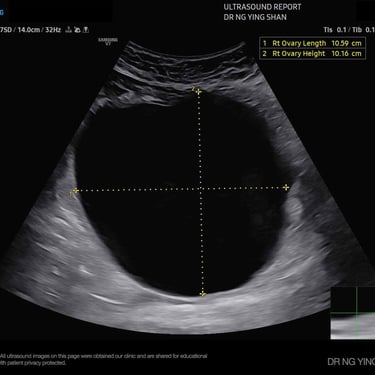

Ovarian cysts (fluid-filled sacs in the ovary)

Ovarian Cyst